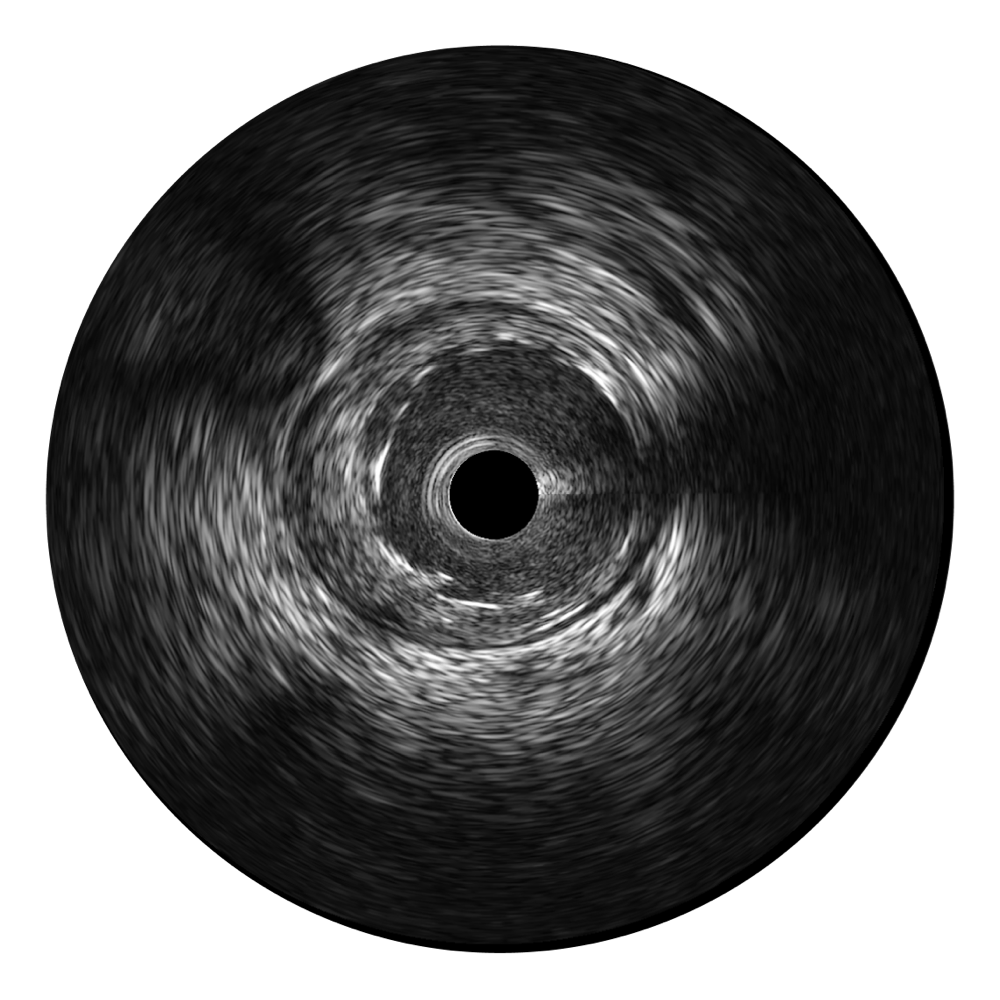

传统IVUS图像

对比传统IVUS导管成像,银河集团官网宽频IVUS图像的近场支架梁显影更细腻,远场中膜外血管仍清晰可辨,兼顾远中近,兼顾分辨力与穿透深度